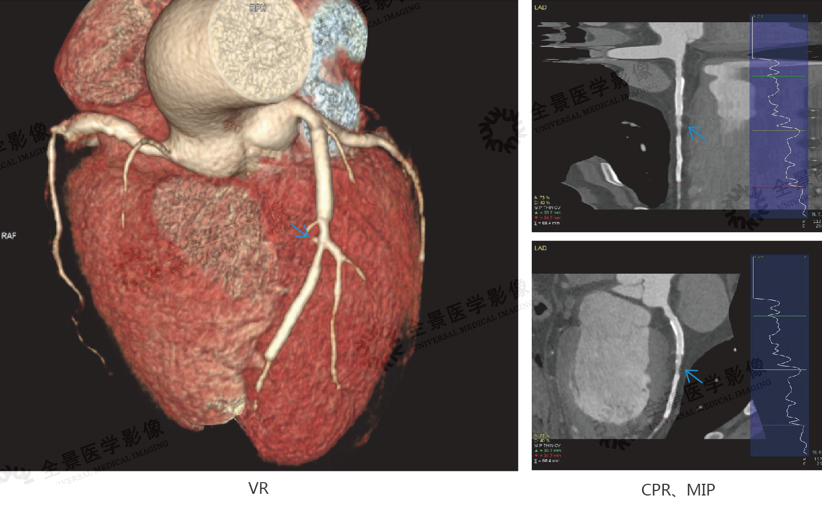

案例2:冠状动脉CTA:支架植入后的治疗评估

中年男性,病史:支架植入术后近10年

结论:左前降支近段、中段支架植入术后,管腔尚通畅,两支架间及中段支架远端开口处钙化斑块,管腔轻-中度狭窄。